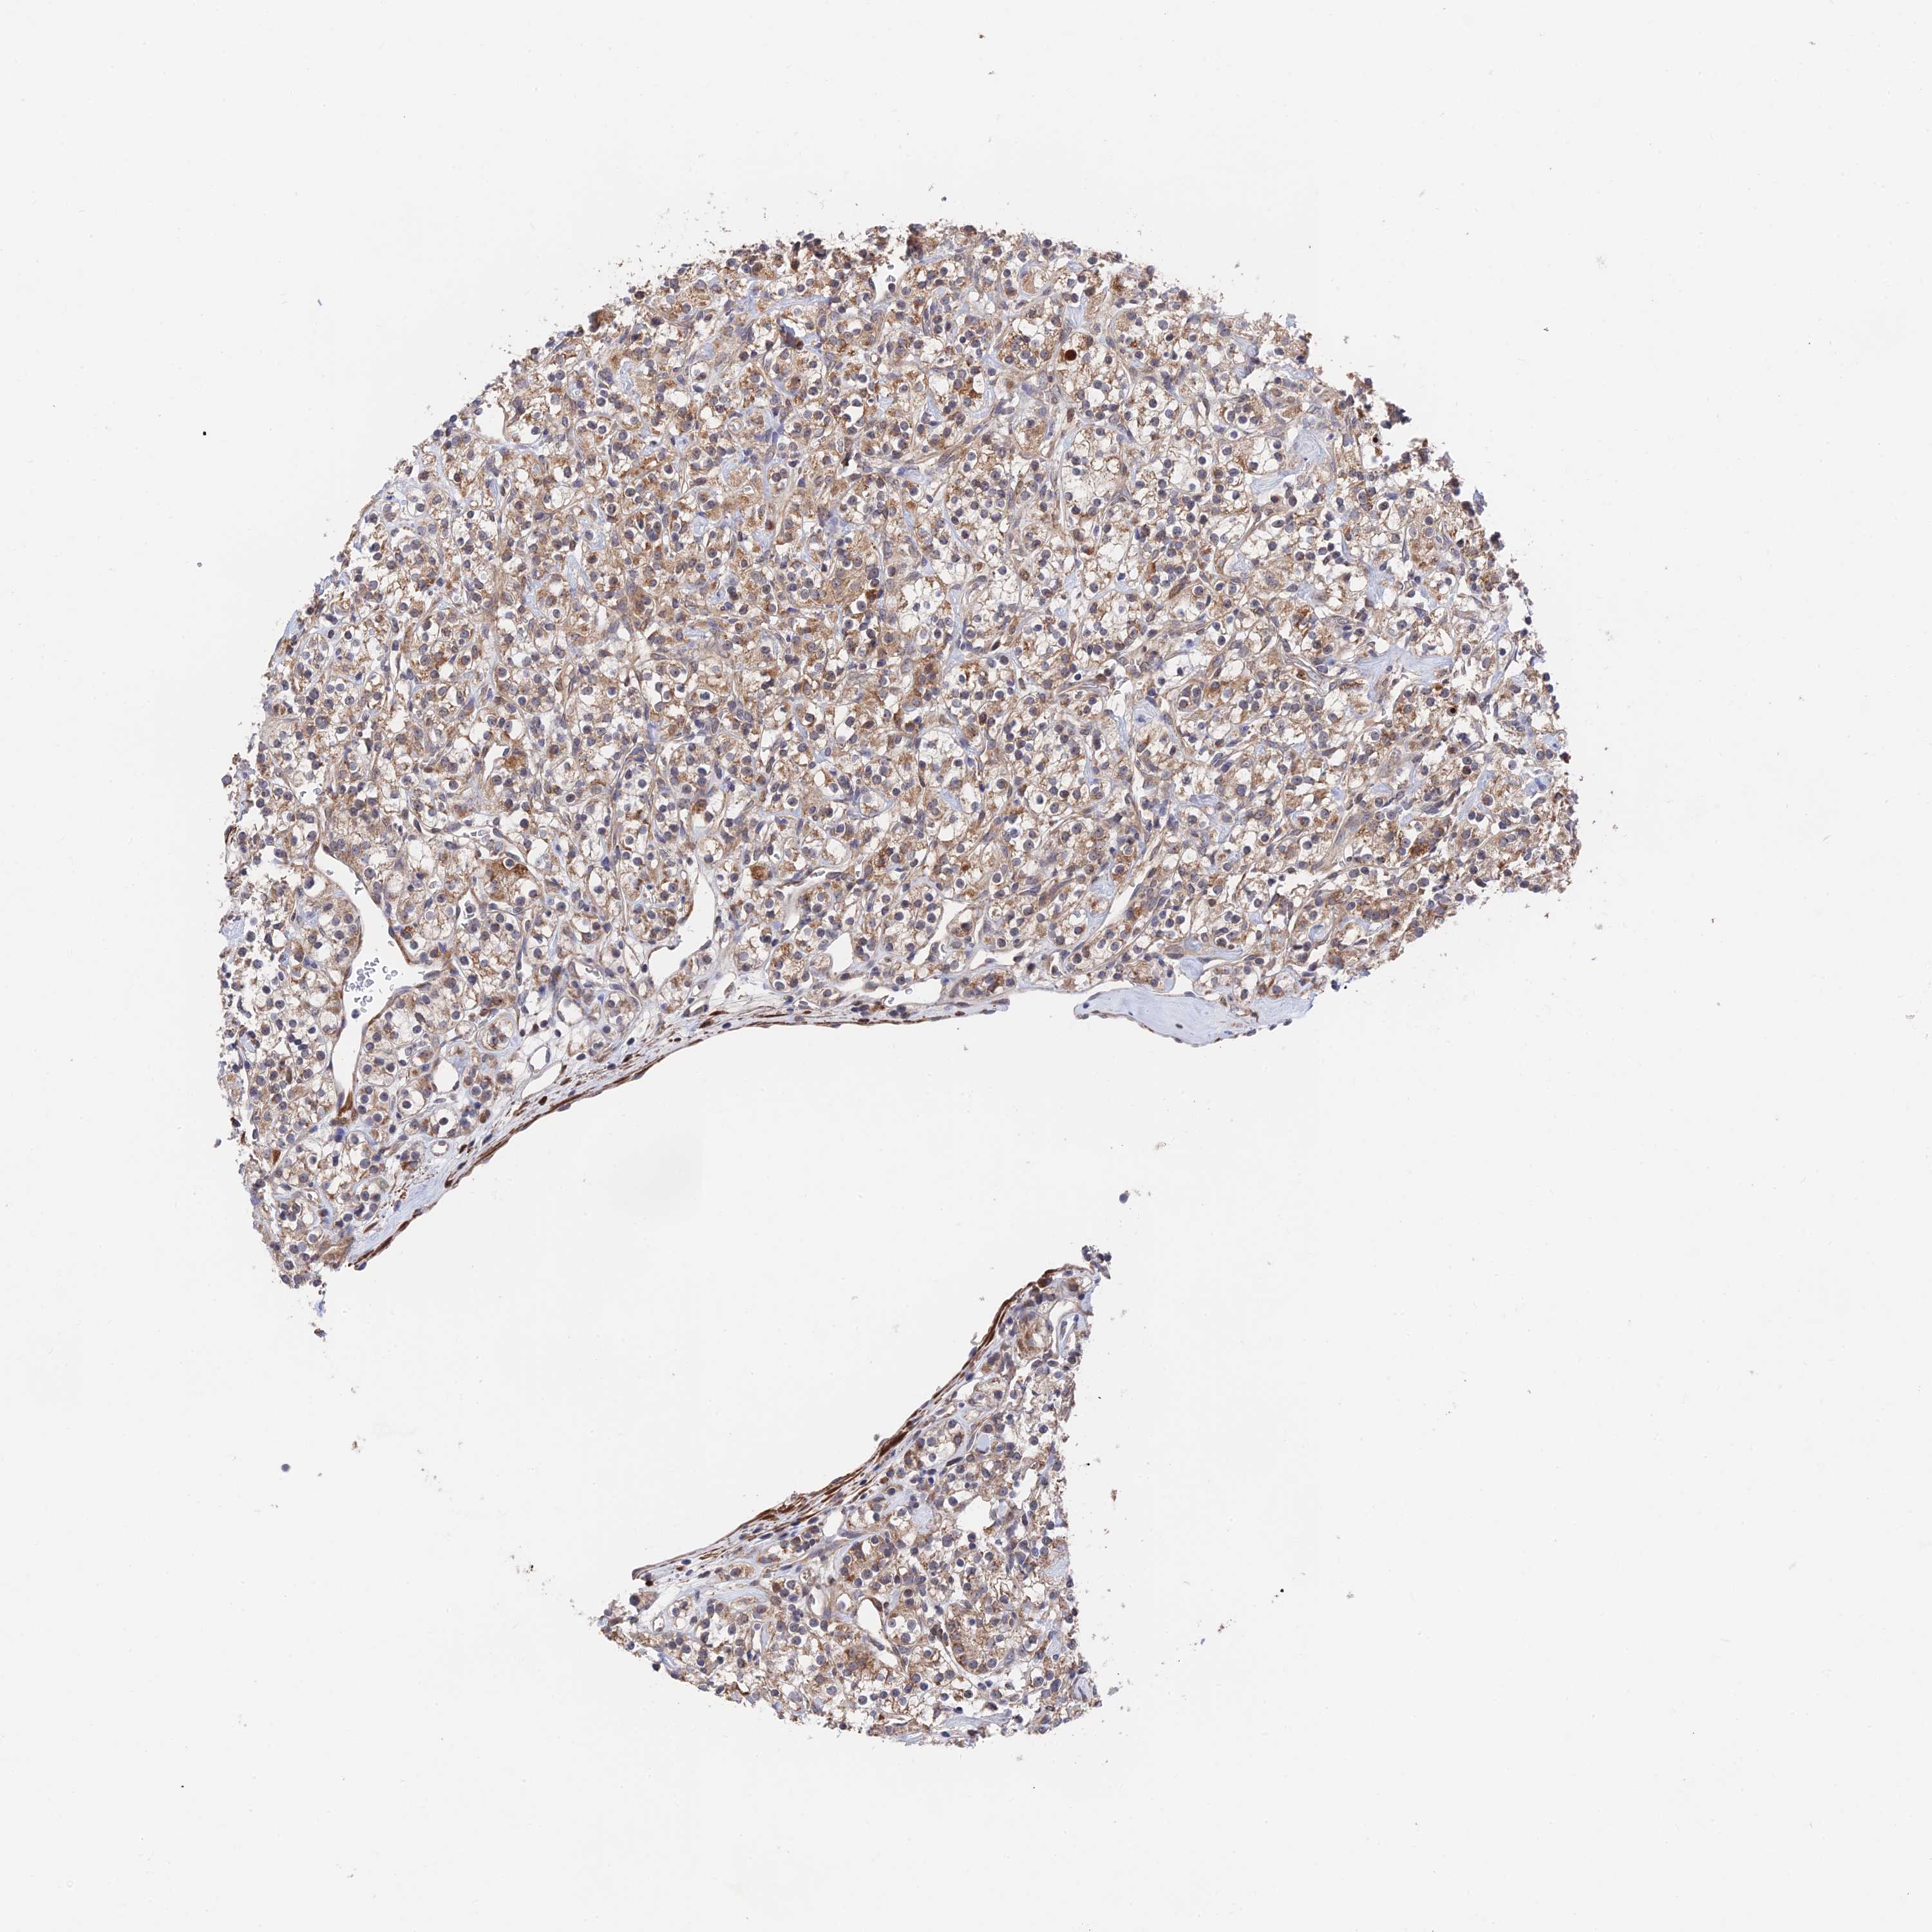

KIDNEY RENAL CLEAR CELL CARCINOMA (VALIDATION) - Interactive survival scatter ploti

The Survival Scatter plot shows the clinical status (i.e. dead or alive) for all individuals in the patient cohort, based on the same data that underlies the corresponding Kaplan-Meier plots. Patients that are alive at last time for follow-up are shown in blue and patients who have died during the study are shown in red.

The x-axis shows the expression levels (FPKM) of the investigated gene in the tumor tissue at the time of diagnosis. The y-axis shows the follow-up time after diagnosis (years). Both axes are complimented with kernel density curves demonstrating the data density over the axes. The top density plot shows the expression levels (FPKM) distribution among dead (red) and alive patients (blue). The right density plot shows the data density of the survived years of dead patients with high and low expression levels respectively, stratified using the cutoff indicated by the vertical dashed line through the Survival Scatter plot. This cutoff is automatically defined based on the FPKM cutoff that minimizes the p-score. The cutoff can be changed by dragging the vertical line or by entering a cutoff value in the square labeled "Current cut-off".

Under the Survival Scatter plot the p-score landscape (black curve; left axis) is shown together with dead median separation (red curve; right axis). Dead median separation is the difference in median mRNA expression between patients who have died with high and low expression, respectively. It is calculated as follows: median FPKM expression of dead patients with high expression - median FPKM expression of dead patients with low expression. This is intended to aid the user in visually exploring custom cutoffs and the associated p-scores and dead median separation.

Individual patient data is displayed and can be filtered by clicking on one or more of the category buttons on the top of the page. Categories describing expression level and patient information include: high, low, alive, dead, female, male and tumor stages. The scale of the x-axis can be toggled between linear and log-scale by clicking on the "x log" button. Mouse-over function shows TCGA ID, patient information and mRNA expression (FPKM) for each patient.

& Survival analysisi

Kaplan-Meier plots summarize results from analysis of correlation between mRNA expression level and patient survival. Patients were divided based on level of expression into one of the two groups "low" (under cut off) or "high" (over cut off). X-axis shows time for survival (years) and y-axis shows the probability of survival, where 1.0 corresponds to 100 percent.

ZNF320 is not prognostic in Kidney Renal Clear Cell Carcinoma (validation)

Best expression cut offi

: 17.57

P scorei

N/A

TCGA RNA samplesi

Normal distribution across the dataset is visualized with box plots, shown as median and 25th and 75th percentiles. Points are displayed as outliers if they are above or below 1.5 times the interquartile range. FPKM values of the individual samples are presented next to the box plot.

Average pTPM 33.3

Number of samples 100